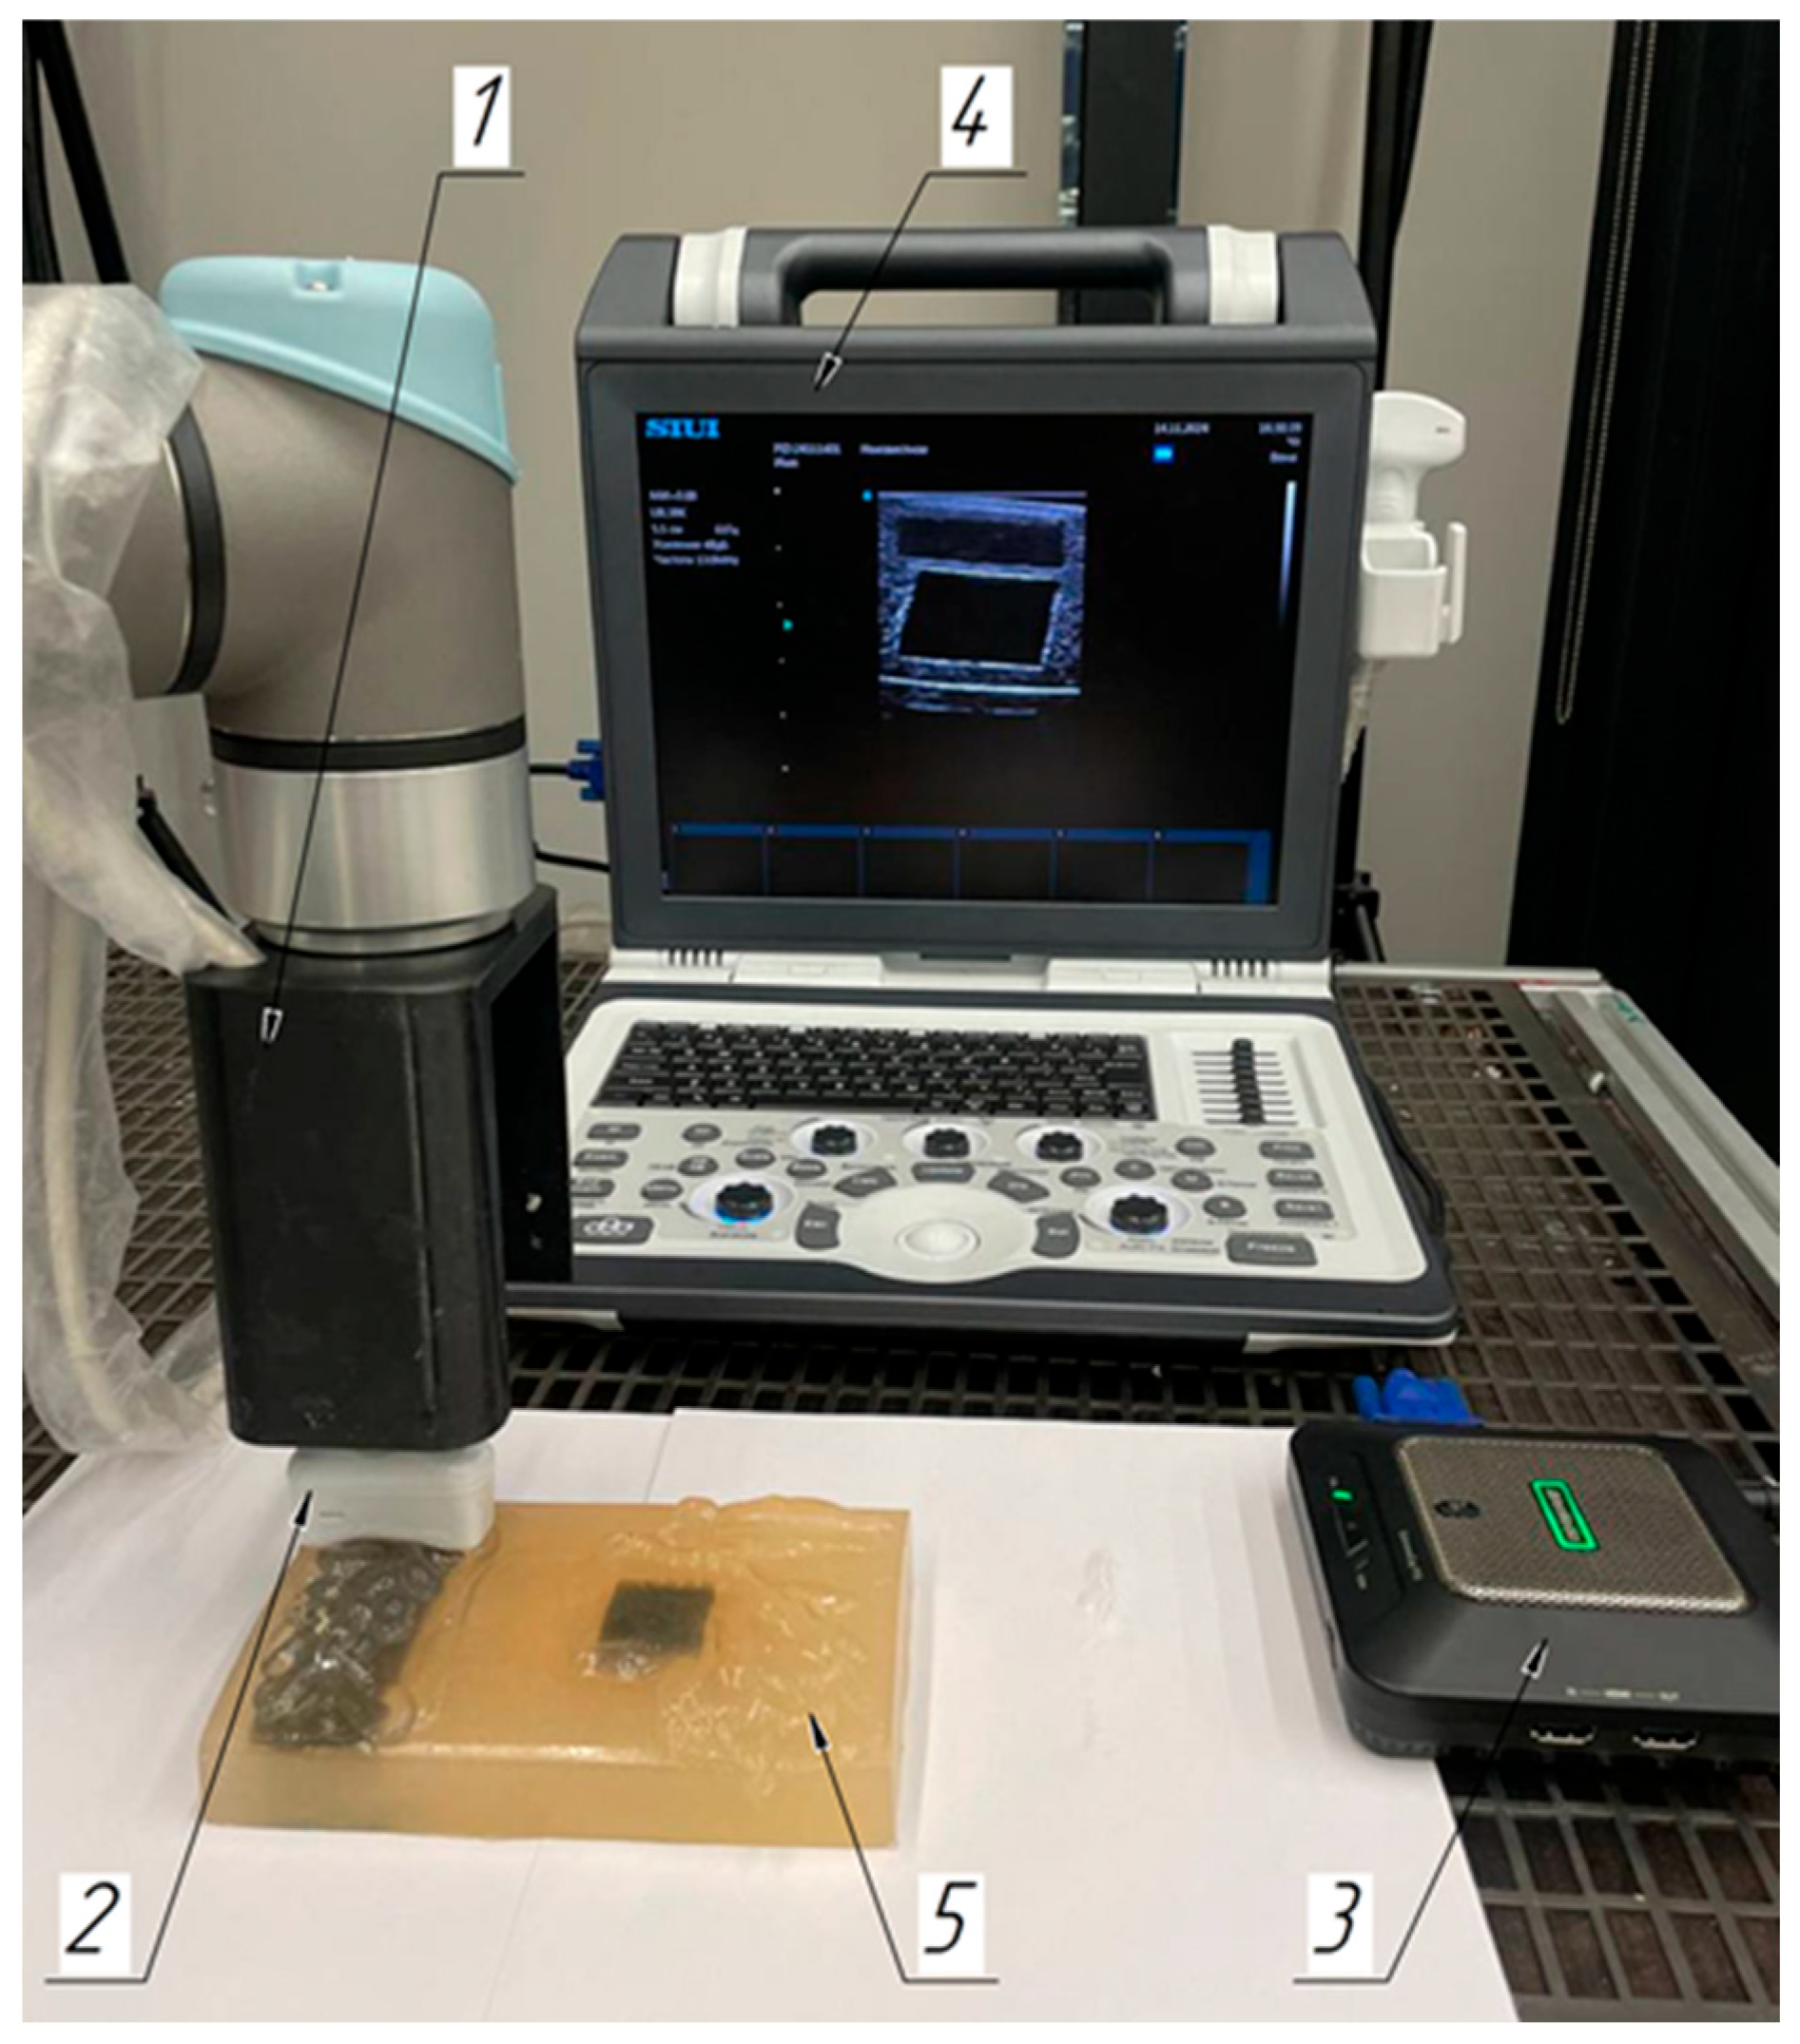

2.1. Laboratory Facilities Diagram

2.3. Robotic Scanning

2.4. Soft Tissue Phantom Development

3.2. Verification of the Methodology for Constructing the Soft Tissue Volumetric Models